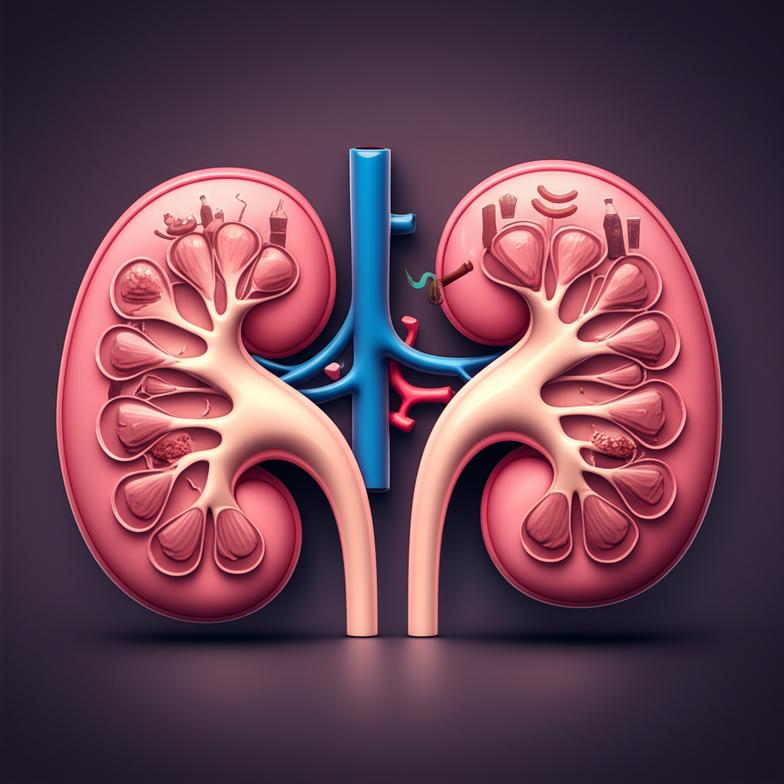

ไตเป็นอวัยวะสำคัญคู่หนึ่งที่ทำหน้าที่มากกว่าแค่ขับของเสียออกจากร่างกาย หน้าที่หลักของไตได้แก่ การกรองเลือดเพื่อกำจัดของเสียและสารพิษ การรักษาสมดุลของน้ำ เกลือแร่ และกรด-ด่างในร่างกาย การผลิตฮอร์โมนที่ควบคุมความดันโลหิต การสร้างเม็ดเลือดแดง และการรักษาสุขภาพกระดูก เมื่ออายุมากขึ้น หรือจากการสัมผัสกับปัจจัยเสี่ยงต่างๆ ไตจะเริ่มเสื่อมประสิทธิภาพลง กระบวนการนี้มักเกิดขึ้นอย่างช้าๆ และเงียบเชียบ โดยที่ผู้ป่วยอาจไม่แสดงอาการจนกว่าการทำงานของไตจะลดลงไปมาก หนึ่งในตัวชี้วัดสำคัญคืออัตราการกรองของไต (Glomerular Filtration Rate หรือ GFR) ที่จะลดลงตามวัย รวมถึงการเปลี่ยนแปลงของโครงสร้างไต เช่น การแข็งตัวของเส้นเลือดฝอยในไต (glomerulosclerosis) และการเกิดพังผืดในเนื้อไต (interstitial fibrosis) ซึ่งล้วนส่งผลให้ความสามารถในการกรองและรักษาสมดุลของไตลดลงอย่างต่อเนื่อง การทำความเข้าใจในกลไกเหล่านี้ช่วยให้เราสามารถวางแผนการดูแลสุขภาพไตเชิงป้องกันได้อย่างมีประสิทธิภาพ

- การลดลงของจำนวนหน่วยไตที่ทำงาน (nephrons)

- การลดลงของหลอดเลือดที่มาเลี้ยงไต

- การเปลี่ยนแปลงของโครงสร้างเนื้อไต เช่น การหนาตัวของผนังเส้นเลือด